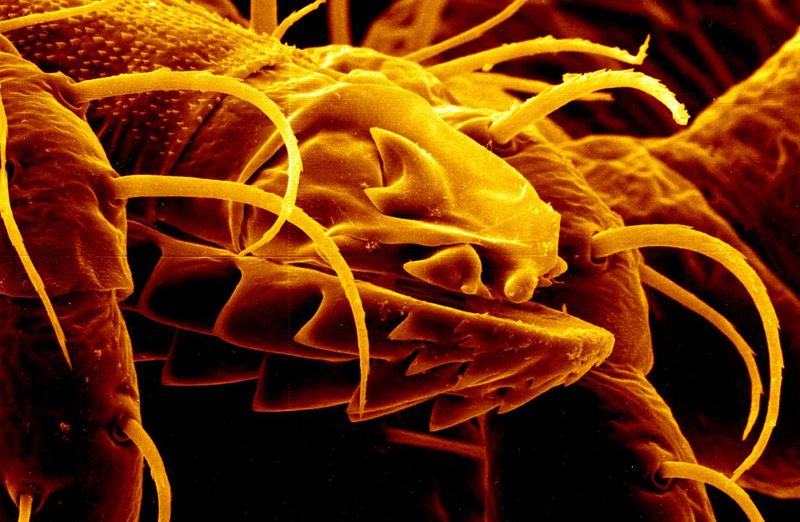

In a new study, published in the journal PLOS One today, researchers led by Dr Pier Paolo Petrone of the University Federico II of Naples have reported what they claim might be the best example of preserved central nervous system tissue ever discovered in human archaeological remains. Using scanning electron microscopy and advanced image processing tools, the team closely studied the vitrified brain to discover a number of distinct structures that appear to be “exceptionally well-preserved” neurons and axons from a human brain and spinal cord.

“The discovery of a vitrified brain was really exceptional, but the finding in it of an entire central nervous system made up of neurons and axons was absolutely astonishing,” Dr Pier Paolo Petrone, lead study author and a forensic anthropologist at University Federico II of Naples, told IFLScience.

On top of this, they also found a number of proteins from human brain tissue, further confirming that this is not simply a random shiny black rock. By identifying the specific proteins, the team were even able to gain insight into which parts of the brain were included in this specimen.

“Analysis of this black glassy material showed the preservation of several proteins highly expressed in the various parts of the human brain: cerebral cortex, basal ganglia, midbrain, pituitary gland, amygdala, cerebellum, hippocampus, hypothalamus, and spinal cord,” explained Dr Petrone.

“These genes are exceptionally significant for neuronal functions since their mutations were detected in patients with brain pathologies. For example, MED13L, whose related protein was found in the glassy brain, was found particularly abundant in adult cerebellum and its mutations were detected in patients with intellectual disability,” he added.